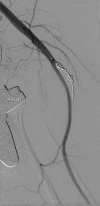

Coil embolization of an aberrant posterior tibial artery pseudoaneurysm after total knee arthroplasty

Arterial injury is a recognized but rare complication of total knee arthroplasty. These injuries, however, can be exceptionally devastating and potentially result in limb loss. Presentation may be delayed with symptoms associated with mass effect rather than with ischemia. We describe treatment of a patient with presentation delayed 2 weeks. In addition, the patient's arterial branch pattern demonstrated aberrant anatomy with high takeoff of the posterior tibial artery. This patient was successfully treated with transcatheter coil embolization. The current treatment options and published literature are reviewed.